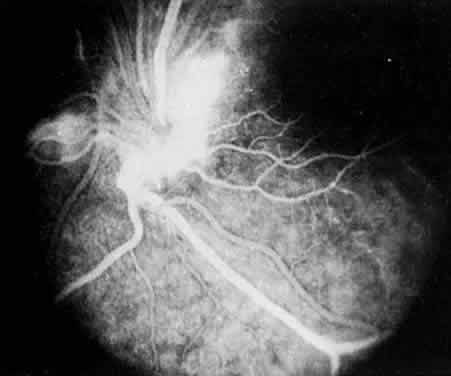

FLUORESCEIN ANGIOGRAPHY AND VITREOUS FLUOROPHOTOMETRY In pars planitis, fluorescein angiography shows diffuse leakage from the retinal venules and capillaries, without any predilection for the inferior retinal vasculature (Figs. 5 and 6).28 Similarly, vitreous fluorophotometry in patients with pars planitis also shows no predilection for vascular leakage in the inferior peripheral retina.29 These findings suggest that snowbank is most likely a sequela from ocular inflammation, that inferior peripheral retina periphery is not the source of inflammation in pars planitis, and that pars planitis is not a localized inflammatory response of the inferior retina.